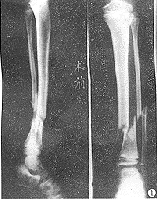

X线正位片应包括胫腓骨全长,以免漏诊。X线可见骨折线、碎骨片、断端移位等。

在骨的x线描述上,首先确定骨折的部位,在上l/3、中l/3或下1/3。再确定骨折类型是横断、斜行或螺旋型骨折,骨折有无粉碎,以及是否多段。侧方移位严重则愈合很难。×线片上不易确定上下骨折段的旋转移位,要从临床上来判断和纠正。